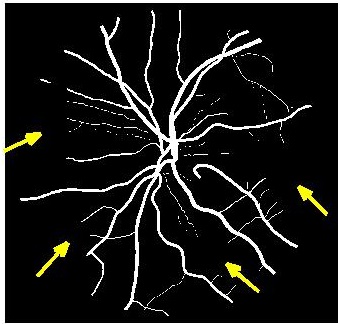

4.2 Retinal Blood Vessel Segmentation Results

We present retinal vessel segmentation results on the DRIVE [16], STARE [6] and CHASEDB1 [5] datasets with , and images respectively. Original images and manual annotations () are downsampled by to get and sets of from methods trained on [2]. and the sets of were used to train different state-of-the art U-Nets for vasculature segmentation [1]. The average accuracy () and sensitivity () for is summarized in Table 2. Better ISR methods should give higher vessel segmentation accuracy and performance of gives a lower bound on the segmentation error. ’s performance is closest to , and establishes its superiority over all competing methods. Figures 4 (a)-(h) show results of vessel segmentation on an example image. ’s performance is most similar to as is evident from the areas of inaccurate segmentation highlighted by yellow arrows. Most of the methods do not segment the finer vasculature structures, while SSR and SR-RF are unable to segment some of the major arteries.

![]() |

| (a) | (b) | (c) | (d) | (e) | (f) | (g) | (h) |